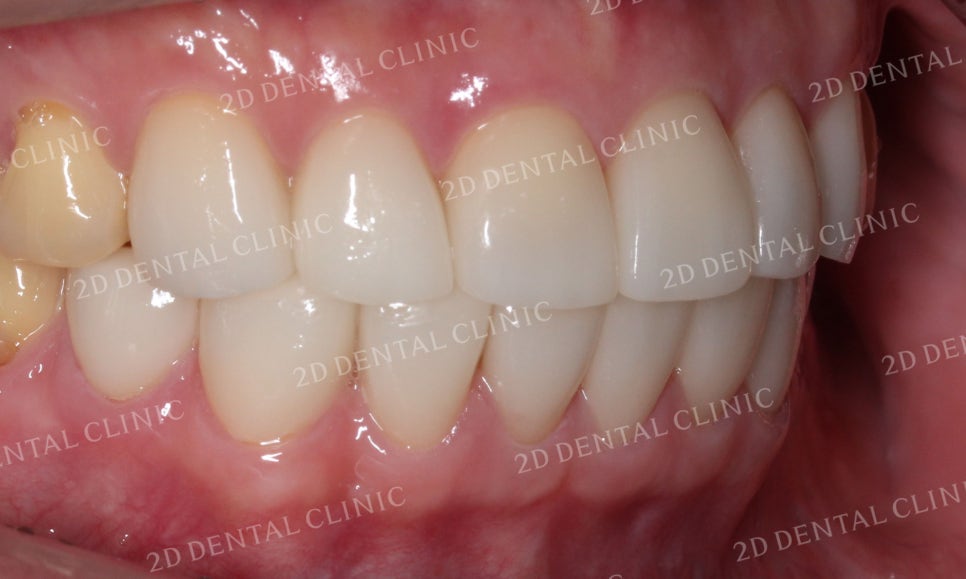

좌측의 안모역시 치아의 뿌리가 드러나고

치간이개가 많이 진행된 모습이었습니다.

블링스 시술 후 벌어졌던 공간이 채워지고

말끔해진 상태입니다!